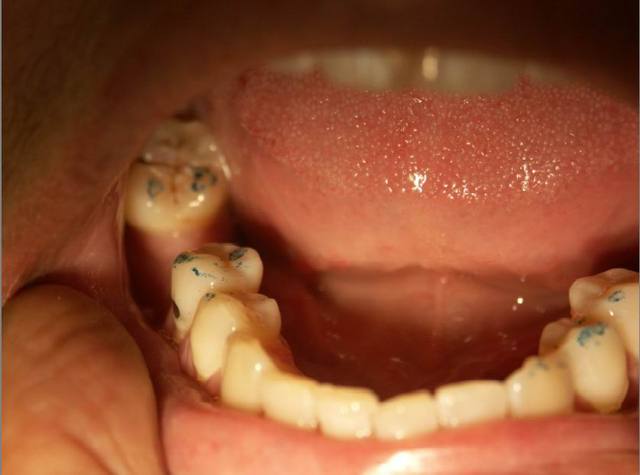

Autre cas .........d occluso.

Pour le cas d occluso ..........

Patiente de 43 ans soufrant de coxo-arthrose handicapante depuis + 10 ans. Douleurs permanente, agravée par la station debout.

Sur avis de son medecin, a refusé de se faire operer suite echec aux traitements medicaux.

1 ere seance de meulages mardi 1/2/05. Disparition de ses douleurs permanentes. Sensation de relachement et de dentente musculaire surtout au niveau des hanches.

2e senace aujourd hui. Pas de recidive au niveau des hanches, mais douleur cervicale et craquement ATM....deviation de la Md à l'ouverture....observable sur la photo 2

Meulages des dents marquées en bleu.

Disparition de la douleur cervicale en fin de meulage.

Persistance de craquement ATM et de deviation de la Md.

Prochaine seance mardi prochain.